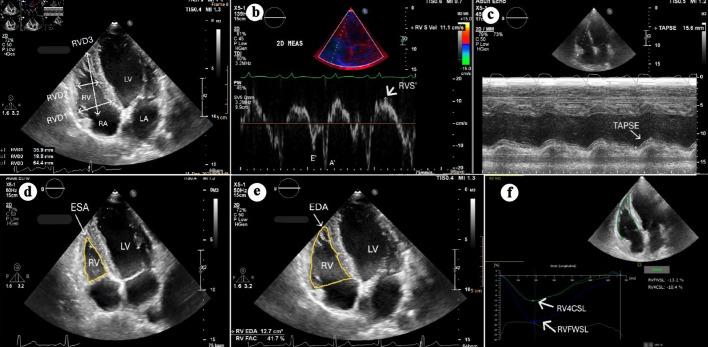

Background: Right ventricular (RV) diameters and systolic function are strong predictors of outcomes and major adverse cardiovascular events (MACEs) in acute myocardial infarction (AMI). This study evaluated RV parameters via echocardiography in AMI patients and assessed their changes 1 month after discharge.

Methods: A prospective observational study was conducted on 133 consecutive patients with their first AMI. RV diameters and systolic function were evaluated with echocardiography within 24 h after successful percutaneous coronary intervention (PCI) and again 1 month after discharge. MACEs were evaluated during hospitalization and at 1 month post discharge.

Results: Men accounted for 69.92% of the participants, with a mean age of 68 years. Reduced right ventricular free wall longitudinal strain (RVFWSL) and right ventricular four-chamber longitudinal strain (RV4CSL) were observed in 62.4% (mean -18.28±8.77%) and 83.34% (mean -14.78±6.94%) of patients, respectively. Right ventricular longitudinal strain (RVLS) was significantly lower in the ST-elevation myocardial infarction (STEMI) group and Killip III-IV patients. RV basal and mid diameters (RVD1, RVD2) were larger in right coronary artery (RCA) and left main artery (LM) lesions than in left anterior descending artery (LAD) and left circumflex artery (LCx) ones (P < 0.05). RVLS correlated significantly with body mass index (BMI), troponin I, and left ventricular ejection fraction (LVEF). After 1 month, RVFWSL and RV4CSL improved significantly, especially in patients without MACEs, Killip III-IV, and single-vessel lesions.

Conclusions: RV diameters varied with the culprit lesion and remained stable after 1 month. RVLS was significantly reduced in AMI, especially in STEMI and Killip III-IV, correlating with LVEF. After 1 month, RVLS improved faster, particularly in patients without MACEs, Killip III-IV, or single-vessel lesions.